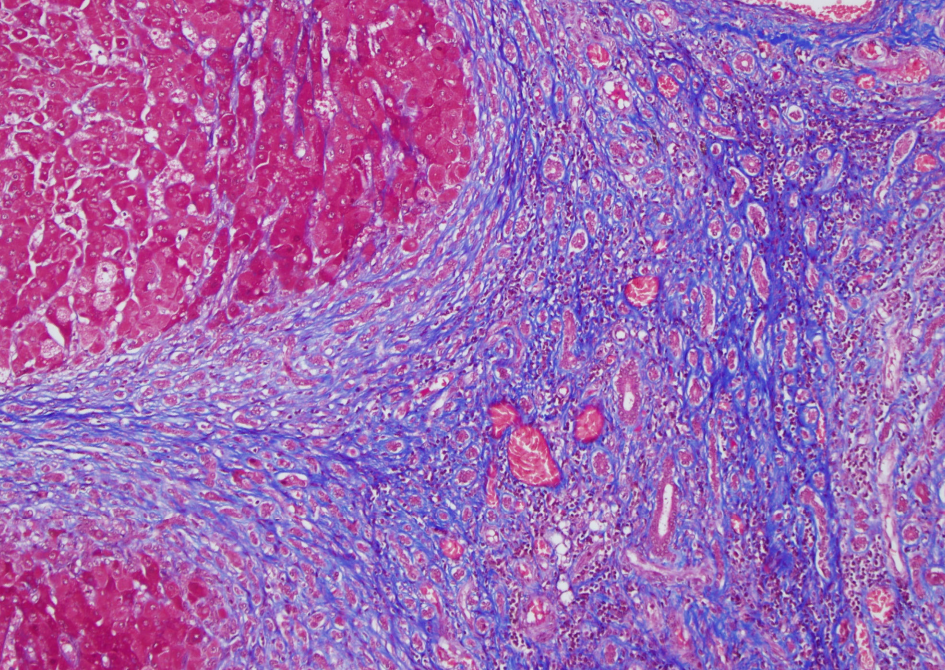

Special stain for cirrhosis

Trichrome- stains for fibrosis (blue)